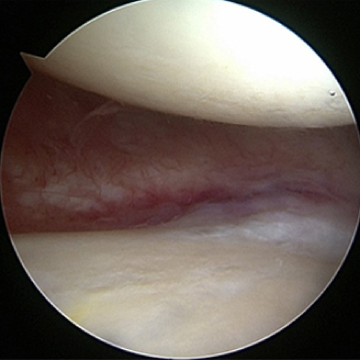

관절내시경 수술 전

관절 내시경 수술 후

노화된 어깨의 관절낭을 절제해 간격을 넓혀주는 수술방법

ㆍ환자 동의를 받은 자료이며, 이미지 사진은 실물과 다를 수 있습니다.

ㆍ2016.09.30 관절내시경 당일 치료 전, 후 사진입니다.